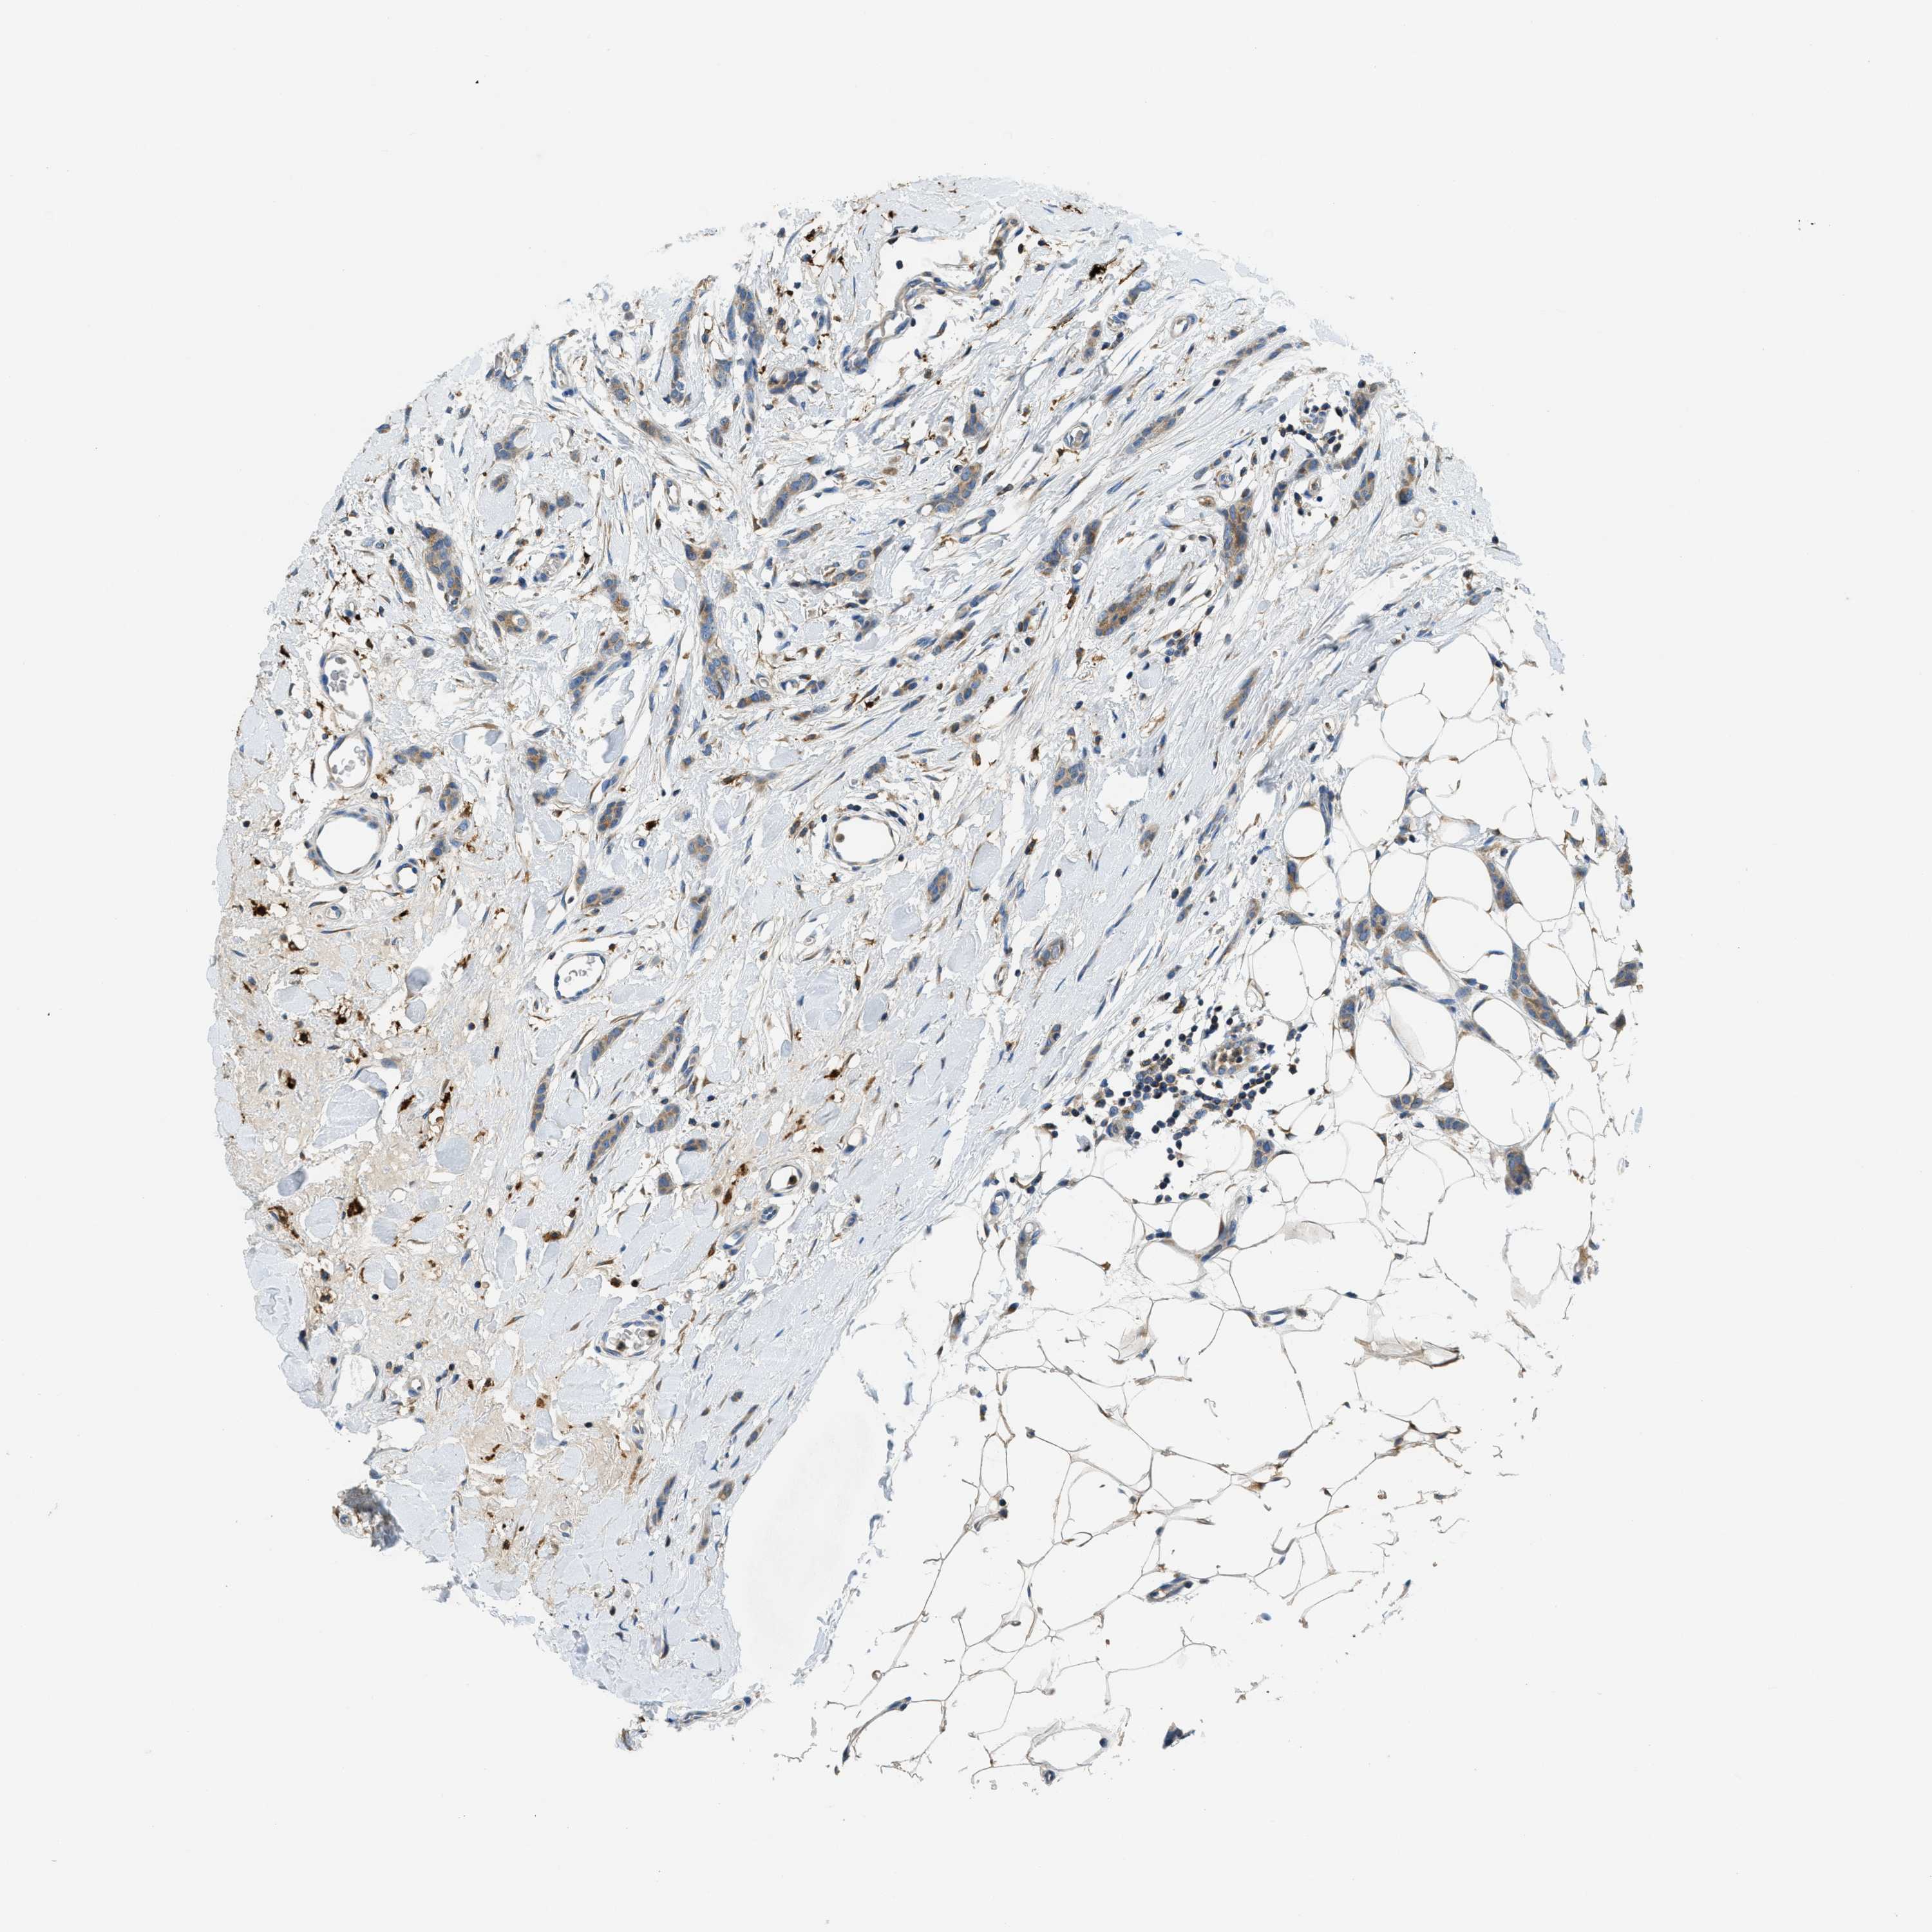

CANCER BREAST CANCER Show tissue menu

BRCA TCGA BRCA VALIDATION PROTEIN EXPRESSION

ANTIBODIES

AND

VALIDATION